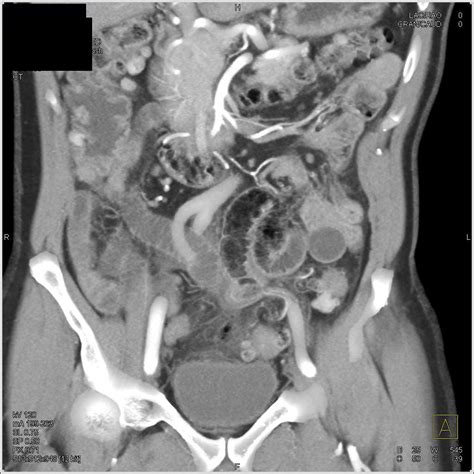

Diagnosing Diverticulitis Sigmoid Colon

Diagnosing diverticulitis sigmoid colon involves a combination of medical history, physical examination, and diagnostic tests. The diagnostic process typically includes:

• Imaging Tests: Imaging tests such as a CT scan or MRI can provide detailed images of the colon and help confirm the diagnosis.

• Perforation: A hole in the colon wall can allow stool to leak into the abdominal cavity, leading to peritonitis.

• Abscess: An infected pocket of pus can form near the colon.